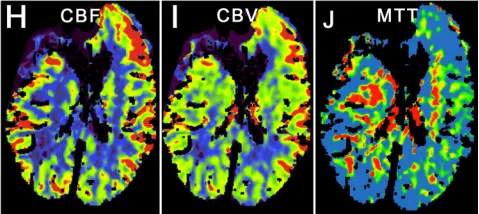

患者随后接受经右侧额部翼点入路开颅术行动脉瘤夹闭术,手术过程顺利。术后影像证实动脉瘤闭塞有效,无并发症。术后脑灌注成像显示一处术前已知的陈旧性脑梗死区域。患者术后接受随访监测,时长23.9个月。